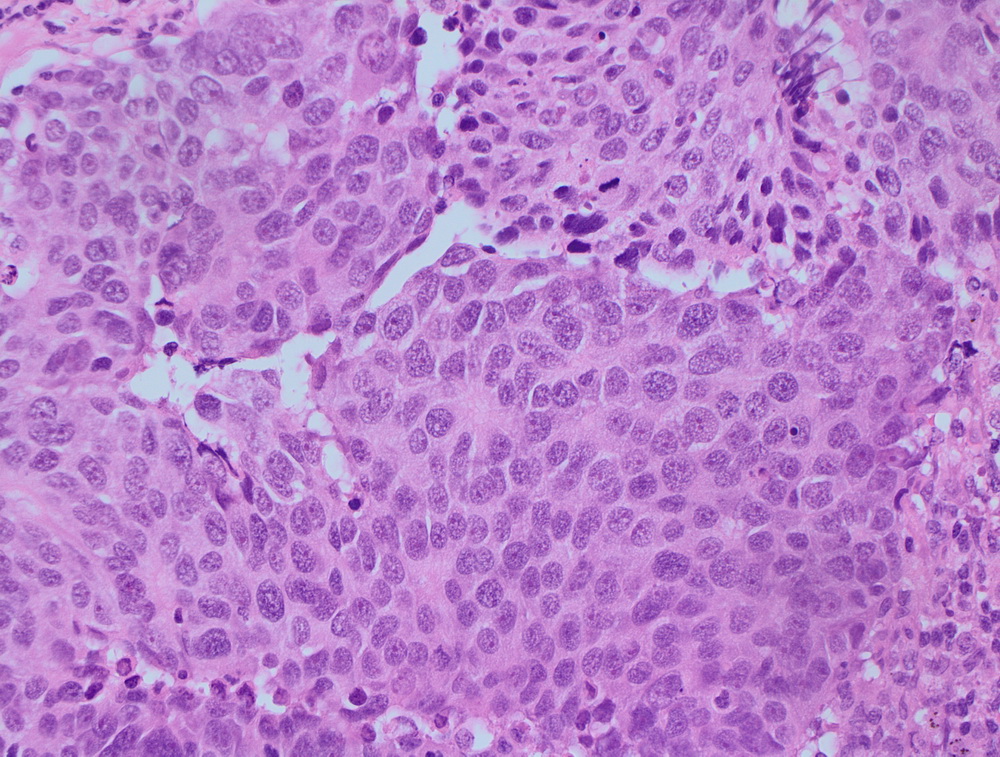

Окрашенные срезы под микроскопом

Инвазивный протоковый рак er 100%. |

Карцинома сигмовидной кишки. |